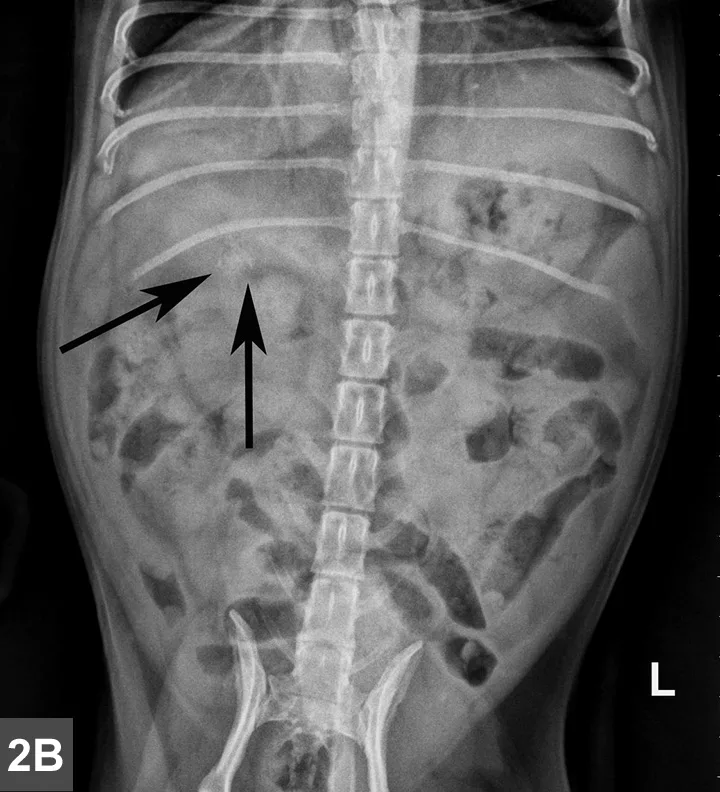

Radiographic Findings

A mottled mineral opacity measuring ~12 mm in diameter is seen just caudal to the last right rib in the VD view, near the pyloroduodenal junction (Figure 2B, black arrows), and superimposed over the pylorus in the lateral view (Figure 2A, black arrows). This opacity could be a foreign body or a mineralized mass or lymph node. Heterogeneous soft tissue material, compatible with ingesta, is present in the gastric lumen as well as throughout the intestines, but no abnormal distention is evident. The liver extends past the costal arch with mild caudal displacement of the gastric axis, consistent with mild hepatomegaly; the margins are smooth. The remaining viscera and serosal detail are normal.

Figure 2A & B

Same lateral and VD radiographs as in Figure 1A and B showing mineral density just caudal to the last right rib in the VD view (Figure 2B, black arrows) near the pyloroduodenal junction and in the lateral view (Figure 2A, black arrows) superimposed over the pylorus.